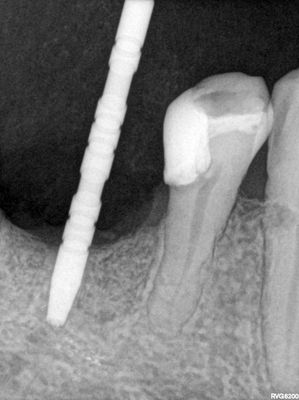

46 implant placement, limited B-l width of bone, slightly narrower implant placed with concurrent buccal bone grafting. 47 relatively straightforward immediate placement with osteotomy underprepared. good stability of both implants. socket grafted, fibrin membrane overtop.